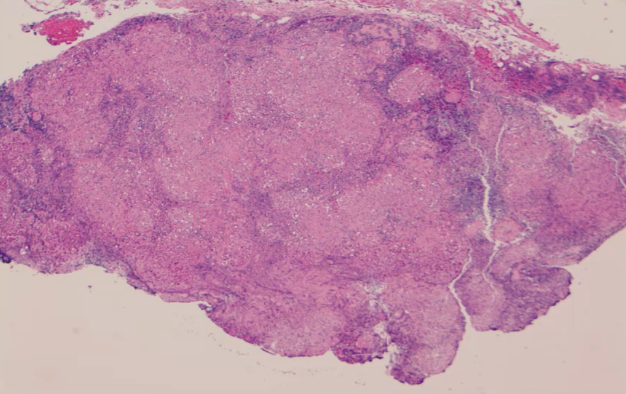

Describe the lymphadenopathy observed in this specimen. How severe would a patient’s fever be and would they have mono or polyclonal B/T cells?

Indicative of an infection (some increase in secondary follicles due to mounting of immune response)

Indicative of neoplasm (cellular atypia and no secondary follicles)